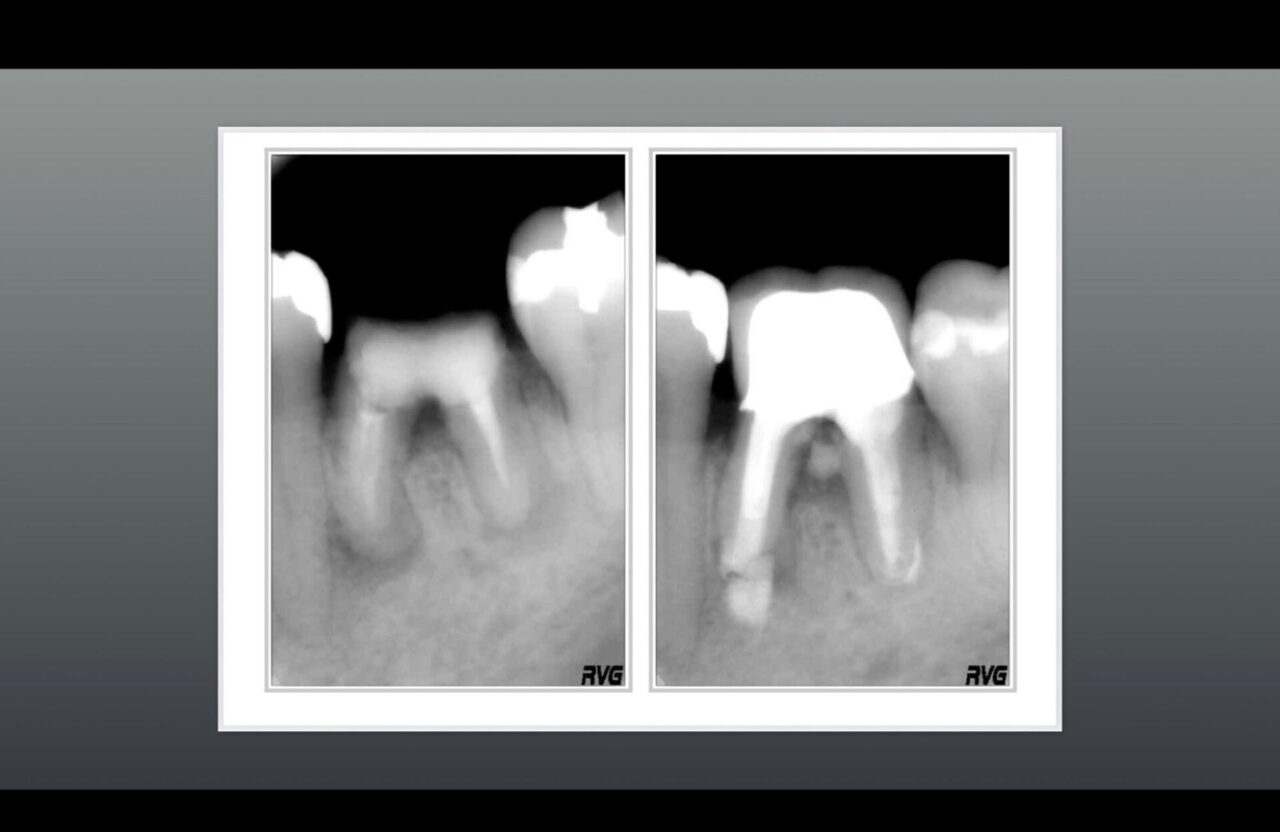

術前と術後のレントゲン➁

術前のレントゲンと術中の口腔内写真、髄床底部に大きなパーフォレーション及びクラックラインが確認できる。

術前のレントゲンと術後のレントゲン、根尖部の骨は再生されており機能させている。

パーフォレーション部の骨も再生されており、適切な修復物が装着され機能している。